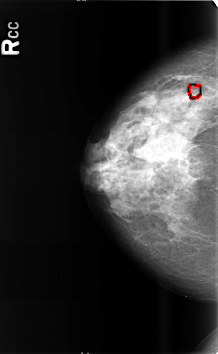

B_3464_1.RIGHT_CC

LEFT_CC LINES 4552 PIXELS_PER_LINE 2952 BITS_PER_PIXEL 12 RESOLUTION 50 NON_OVERLAY

FILE: B_3464_1.RIGHT_CC.OVERLAY

TOTAL_ABNORMALITIES 1

ABNORMALITY 1

LESION_TYPE CALCIFICATION TYPE AMORPHOUS-PLEOMORPHIC DISTRIBUTION CLUSTERED

ASSESSMENT 4

SUBTLETY 3

PATHOLOGY BENIGN

TOTAL_OUTLINES 1

BOUNDARY